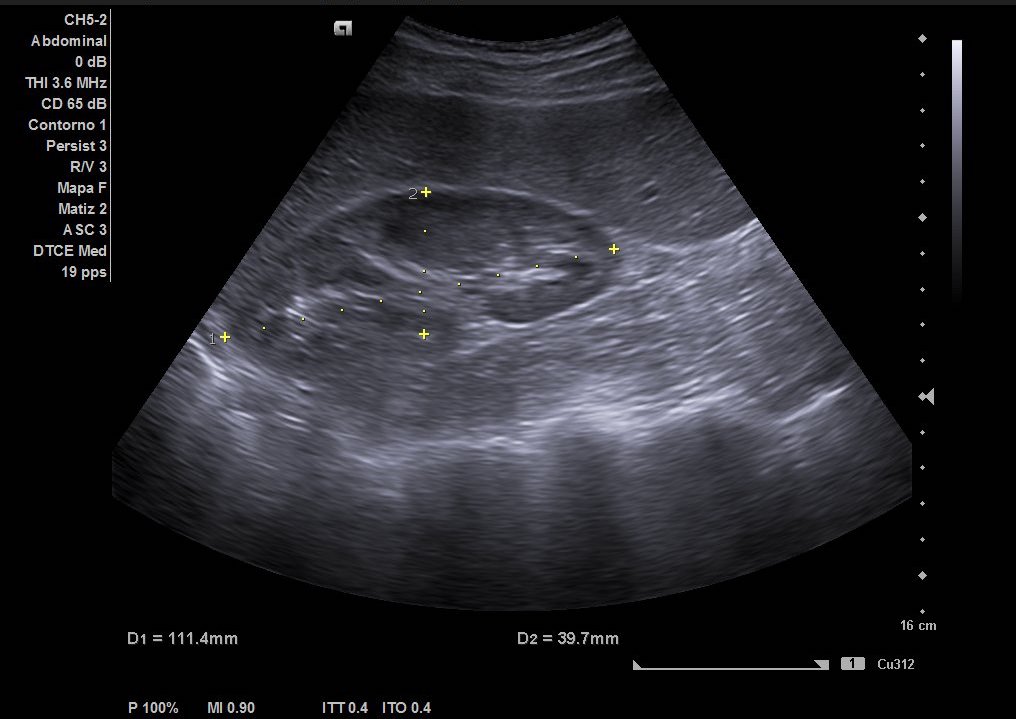

Hallazgos ecográficos

Como hallazgos, observamos dilatación del uréter proximal con hidronefrosis grado II-III. Sin visualización de imágenes compatible con litiasis. Riñón derecho de tamaño y ecoestructura normal sin dilatación de vía excretora. Vejiga vacía y ausencia de liquido libre.

Se deriva a Urgencias Hospitalarias para valoración y tratamiento. Se le realiza analítica sanguínea y de orina sin elevación de reactantes de fase aguda. Se solicita ecografía abdominal reglada, con hallazgos de litiasis en tercio medio de uréter izquierdo que condiciona hidronefrosis retrógrada grado III por lo que se contacta con Urólogo de guardia que cita en consultas externas para valoración.